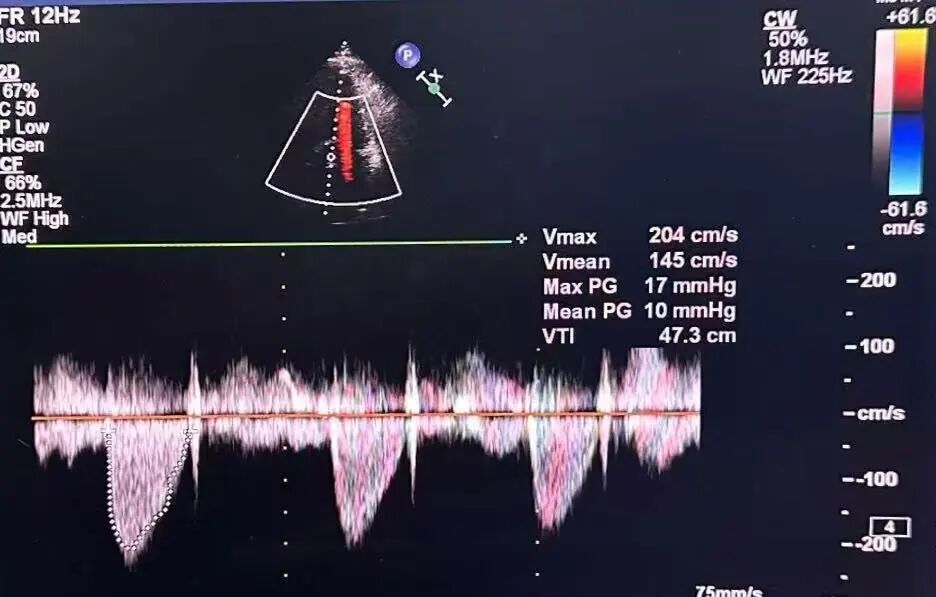

谷兴华教授 山东大学齐鲁医院 锚定终身获益,重视首次干预选择:心脏瓣膜病介入中心成立2年多来,中心核心目标始终保证在解决即刻病症的基础上,护航患者的全生命周期健康管理。 摆在眼前的实际是日益年轻化的患者群体,这意味着我们从手术伊始,就必须将患者未来数十年的生活质量和再次干预风险纳入核心考量,主动规划长远的健康路径。此次患者选择更具耐久的新型干瓣技术,力求减少患者未来再次干预的风险。同时,通过“TAVR+PCI一站式手术”这样的团队协作模式,系统性地处理多重心血管问题,避免分次手术的负担与风险,这正是我们中心一直秉持的“心脏瓣膜病全生命周期管理”理念的实践。让我们一起探索从“治已病”真正迈向“管长远”,让更多的患者获益! 病例特点速览 本次救治的患者,病情呈现“基础病交织、多病变叠加、锚定风险高”三大核心特征。患者为65岁,女性,病变特点TypeI型二叶瓣、轻度钙化,锚定风险大;同时患有冠状动脉粥样硬化性心脏病、慢阻肺(COPD);既往有长期吸烟饮酒史、脑梗死病史、高血压病史、乙肝小三阳病史及腹股沟疝修补手术史,患者STS评分9.32%,外科手术高危,经齐鲁医院瓣膜中心团队评估认为:局麻下“一站式TAVR+PCI”为最优治疗方案,结合患者较年轻,可选择具有长期耐久性的干瓣。 患者病史 主诉:活动后胸闷、憋喘余,加重20余天 既往史:30年前确诊乙肝小三阳,否认其他传染病史;有右腹股沟疝修补手术史,高血压病史,近期规律服药控制。 现病史:患者1年前出现活动后胸闷、憋喘,休息可缓解,为进一步诊治。2月前因“突发意识模糊、口齿不清”于当地医院入院,诊断为“急性脑梗死”,予以微创介入取栓治疗,恢复可,未遗留后遗症。20天前于当地医院再次入院行脑血管支架植入术,术后出现胸闷、憋喘,伴大汗,行心脏超声提示主动脉瓣重度狭窄,并行冠脉造影检查,予以药物治疗。10天前就诊于我院复查心脏超声提示二叶式主动脉瓣,主动脉瓣狭窄(重度)并反流(轻度)。患者现仍感胸闷,双上臂疼痛不适,咳嗽咳痰,日常活动受限。为行进一步治疗就诊于我院,门诊以“主动脉瓣狭窄、冠状动脉粥样硬化性心脏病”收入院; 个人史:吸烟50年,饮酒50年; 体格检查:体温:36℃,脉搏:67次/分,呼吸:18次/分,血压:143/76mmHg; 术前超声提示: 二叶式主动脉瓣主动脉瓣狭窄(重度)并反流(轻度);升主动脉扩张、左心扩大三尖瓣反流(少量);左室充盈异常;CW测最大压差86mmHg,平均压差43mmHg,最大血流速度463cm/s,连续方程法估测主动脉瓣口面积0.78cm² 术前CT评估 Type1型二叶瓣,轻度钙化、左右融合,主动脉瓣环径25.3mm,LVOT直径25.5mm,鱼嘴空间约26.6mm,主要靠瓣环锚定。窦部空间大、左右融合,VTC空间足够,无冠脉风险 ;左室内径正常,主动脉瓣环水平夹角49.6°。外周双侧入路内径可,髂外动脉存在散在钙化、双侧入路能够支持20F大鞘通过,右股低分叉,主动脉弓距弓角可。 个性化手术策略:局麻一站式方案+创新瓣膜精准适配 入路选择:主入路:右侧股动脉(右股分叉上方1cm处穿刺);辅入路:左侧股动脉;器械:20F大鞘; 手术流程规划:局麻下行同期一站式TAVR+PCI,植入ProStyle A®预装干瓣; 瓣膜选型与预处理:瓣膜型号:ProStyle A® AV32;不预扩; 定位与释放方案:初始定位:瓣上3mm处释放,瓣膜自然下滑至工作位,最终目标“0-瓣下5mm位”。 手术过程:局麻一站式操作+创新瓣膜植入,无缝衔接 手术团队按预设方案稳步推进,实现TAVR、PCI与ProStyle A®干瓣植入的无缝衔接: 1.术前准备:完成影像评估、血管通路建立,确认ProStyle A® AV32瓣膜状态; 2.PCI治疗:通过主入路完成左冠造影,前降支、对角支明显狭窄,精准植入两枚支架,恢复冠脉血供; 左冠造影,前降支、对角支病变 PCI后造影,病变血管充盈良好 3.主动脉根部造影:确认主动脉根部解剖结构,并精准跨瓣; 主动脉根部造影 精准跨瓣 4.干瓣植入:将瓣膜输送过弓、过瓣,并精准定位; 输送系统柔顺过弓 精准定位 5.术中评估:释放瓣膜至工作状态,再次造影评估,位置满意,完全释放瓣膜; 工作位评估 32号瓣膜稳定脱钩 6.释放后造影:可见瓣膜位置满意、形态良好,无明显瓣周漏。 最终造影,位置形态良好,无瓣周漏 术后超声探查:位置(瓣下4mm)、形态良好,无瓣周漏,PGmean=10mmHg。 此次手术的成功,体现了山东大学齐鲁医院心脏瓣膜病介入中心秉承的“心脏瓣膜病全生命周期管理”的理念和团队协作的临床能力。面对低龄高风险复杂病例,团队通过术前充分评估、术中精细操作,结合具有长期耐久性的干瓣技术,以一站式方案改善患者症状、提高生活质量并延长寿命,为类似病例的诊疗提供宝贵经验。 专家简介 谷兴华 山东大学齐鲁医院(点击查看专家详细简历)